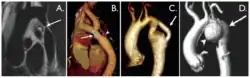

With imaging, resorption of the lower part of the ribs may be seen, due to increased blood flow over the neurovascular bundle that runs there. Prestenotic dilatation of the aortic arch and left subclavian artery, as well as indentation at the site of coarctation results in a classic 'figure 3 sign' on x-ray. The characteristic bulging of the sign is caused by dilatation of the aorta due to an indrawing of the aortic wall at the site of cervical rib obstruction, with consequent poststenotic dilatation. This physiology results in the '3' image for which the sign is named.[5][6][7] When the esophagus is filled with barium, a reverse 3 or E sign is often seen and represents a mirror image of the areas of prestenotic and poststenotic dilatation.[8]

Coarctation of the aorta can be accurately diagnosed with magnetic resonance angiography. In teenagers and adults echocardiograms may not be conclusive.

The severity of coarctation of the aorta can be rated by a combination of the smallest aortic cross-sectional area of the aorta (adjusted for body surface area) as measured by 3D-rendered contrast MRI, as well as mean heart rate–corrected flow deceleration in the descending aorta as measured by phase contrast magnetic resonance imaging.[9]

Aortic coarctation using different imaging techniques[10]

Aortic coarctation using different imaging techniques[10] Coarctation of the aorta